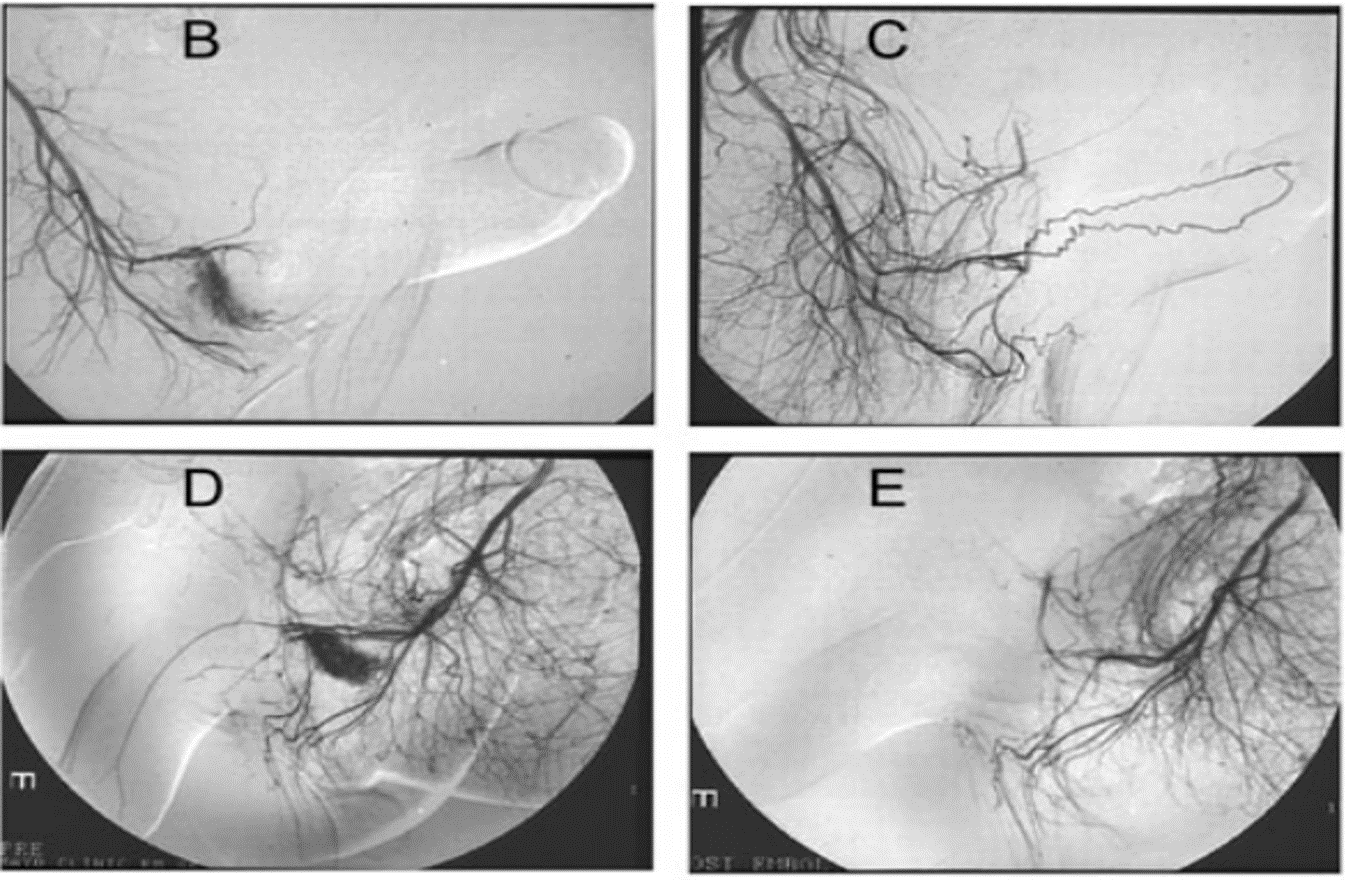

Nút động mạch chọn lọc có thể sử dụng cục máu đông tự thân, gel bọt hoặc bọt biển, hoặc các chất bền vững hơn như coil hoặc keo acrylic. Tỷ lệ thành công lên tới 89%.

Về mặt lý thuyết, việc dùng cục máu đông tự thân có nhiều ưu thế hơn những vật liệu khác, vì cục máu đông tạm thời hàn lại lỗ rò, cho đến khi khối máu tụ bị ly giải, tổn thương động mạch thể hang có thể đã lành. Việc sử dụng các vật liệu bền vững, sẽ chặn vĩnh viễn động mạch và có thể dẫn tới tác dụng không mong muốn liên quan tới rối loạn chức năng tình dục sau này (chủ yếu là rối loạn cương dương). Các tác dụng không mong muốn khác bao gồm hoại thư dương vật, thiếu máu vùng mông, viêm vật hang và áp xe đáy chậu.

Sau nút mạch qua da, tiếp tục theo dõi trong 1 đến 2 tuần. Xác định việc nút mạch thành công hay không có thể dựa trên khám lâm sàng và bằng siêm âm Doppler màu. Nếu có nghi ngờ, việc chụp mạch lại được yêu cầu. Tỷ lệ tái phát từ 30 - 40% sau nút mạch đơn thuần. Kỹ thuật nút mạch tạm thời có chọn lọc có thể bảo tồn được chức năng cương ở 90% người bệnh cương đau dương vật kéo dài thể không thiếu máu.

Nút mạch chọn lọc điều trị cương đau dương vật kéo dài thể không thiếu máu